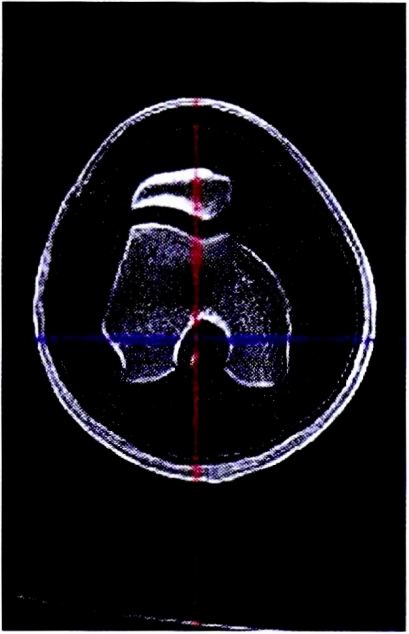

Пациентка К.,16 лет. При осмотре в предоперационном периоде у пациентки были выявлены патологические изменения в правом коленном суставе, характерные для рецидивирующего вывиха надколенника (рис. 2):

- угол Q — 26°;

- индекс Insall—Salvati — 1,5;

- угол конгруэнтности по Merchant — 11° «+»;

- расстояние ТТ—TG — 15 мм;

- антеторсия головки бедренной кости — 14°;

- угол латерализации надколенника, рассчитанный по предложенному способу — 55°.

Рис. 2. Срез компьютерной томографии коленного сустава пациентки К. в аксиальной проекции до операции.

Fig. 2. Section of computed tomography of the knee joint of the patient K. in axial projection before surgery